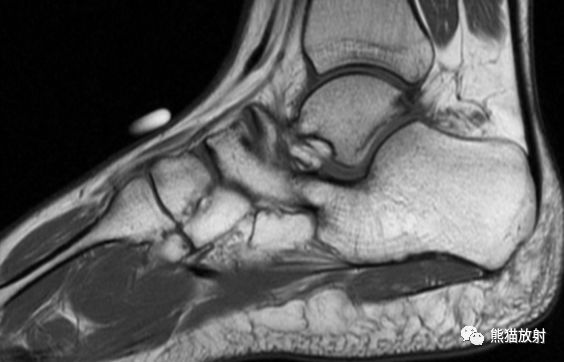

MR矢状PD压脂、矢状T1WI;主要表现:跟骨和舟骨之间可见骨性联合,MR上相应区域无水肿

另外,对软骨性或纤维性联合需借助CT或MRI检查进行判断